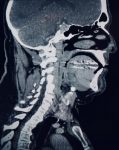

Радиологическое общество Северной Америки ( RSNA ) объявило официальные результаты конкурса RSNA Cervical Spine Fracture AI Challenge . Задача, проводимая RSNA в сотрудничестве с Американским […]… далее